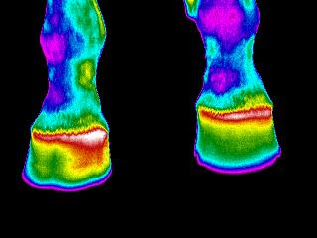

Un casco mal herrado puede tener repercusiones en los músculos de la pierna, espalda, dorso, grupa, tendones, etcétera; afectando la comodidad y rendimiento de su caballo.

La temperatura aumenta del lado que soporta más peso, lo que nos permite detectar fácilmente cómo debe corregirse esta imperfección.